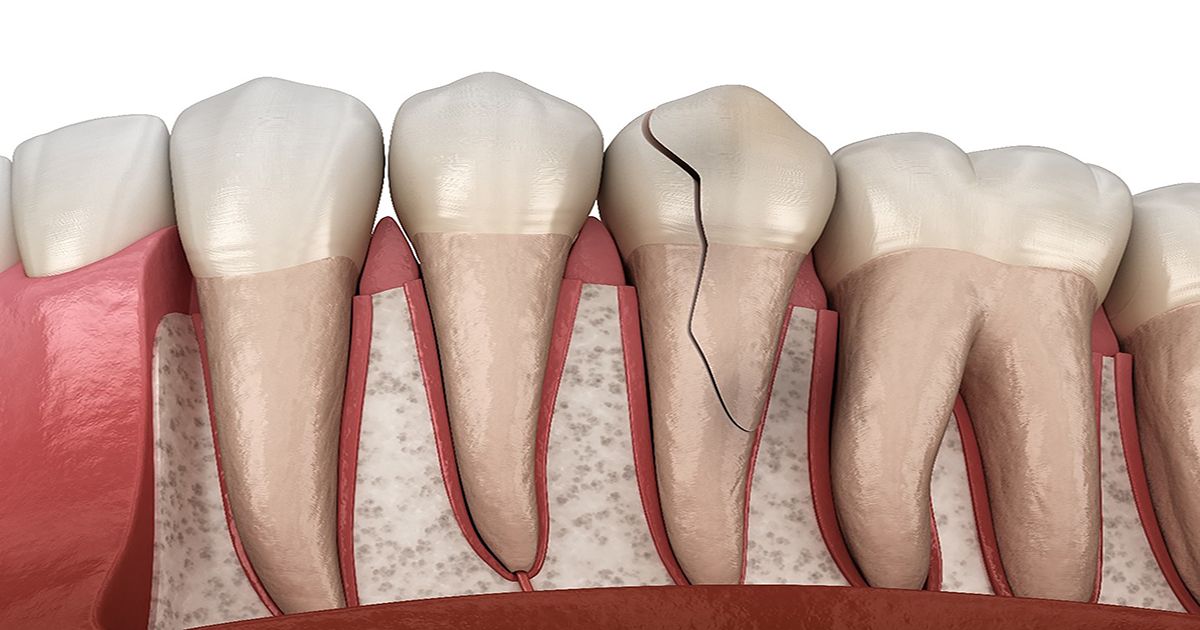

4 best treatments for a cracked tooth You can get a cracked tooth because of any reason. This includes grinding teeth at night, chewing hard food, and much more. When you notice this, the key is to seek help immediately. If you leave it for too long, the issue will get worse. Cracked teeth require…